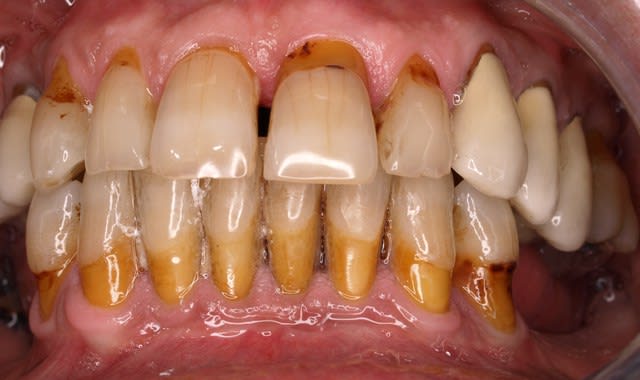

Les 2 images (toujours belle technique opératoire), vont peut être délier les langues (pas sûr que ce soit dans le sens que tu espérais). La aussi il serais intéressant de connaître le plan de traitement et les raisons de ce choix thérapeutique.

REPONSE: ci joint photos du depart.ttt un bridge de contention avec paro